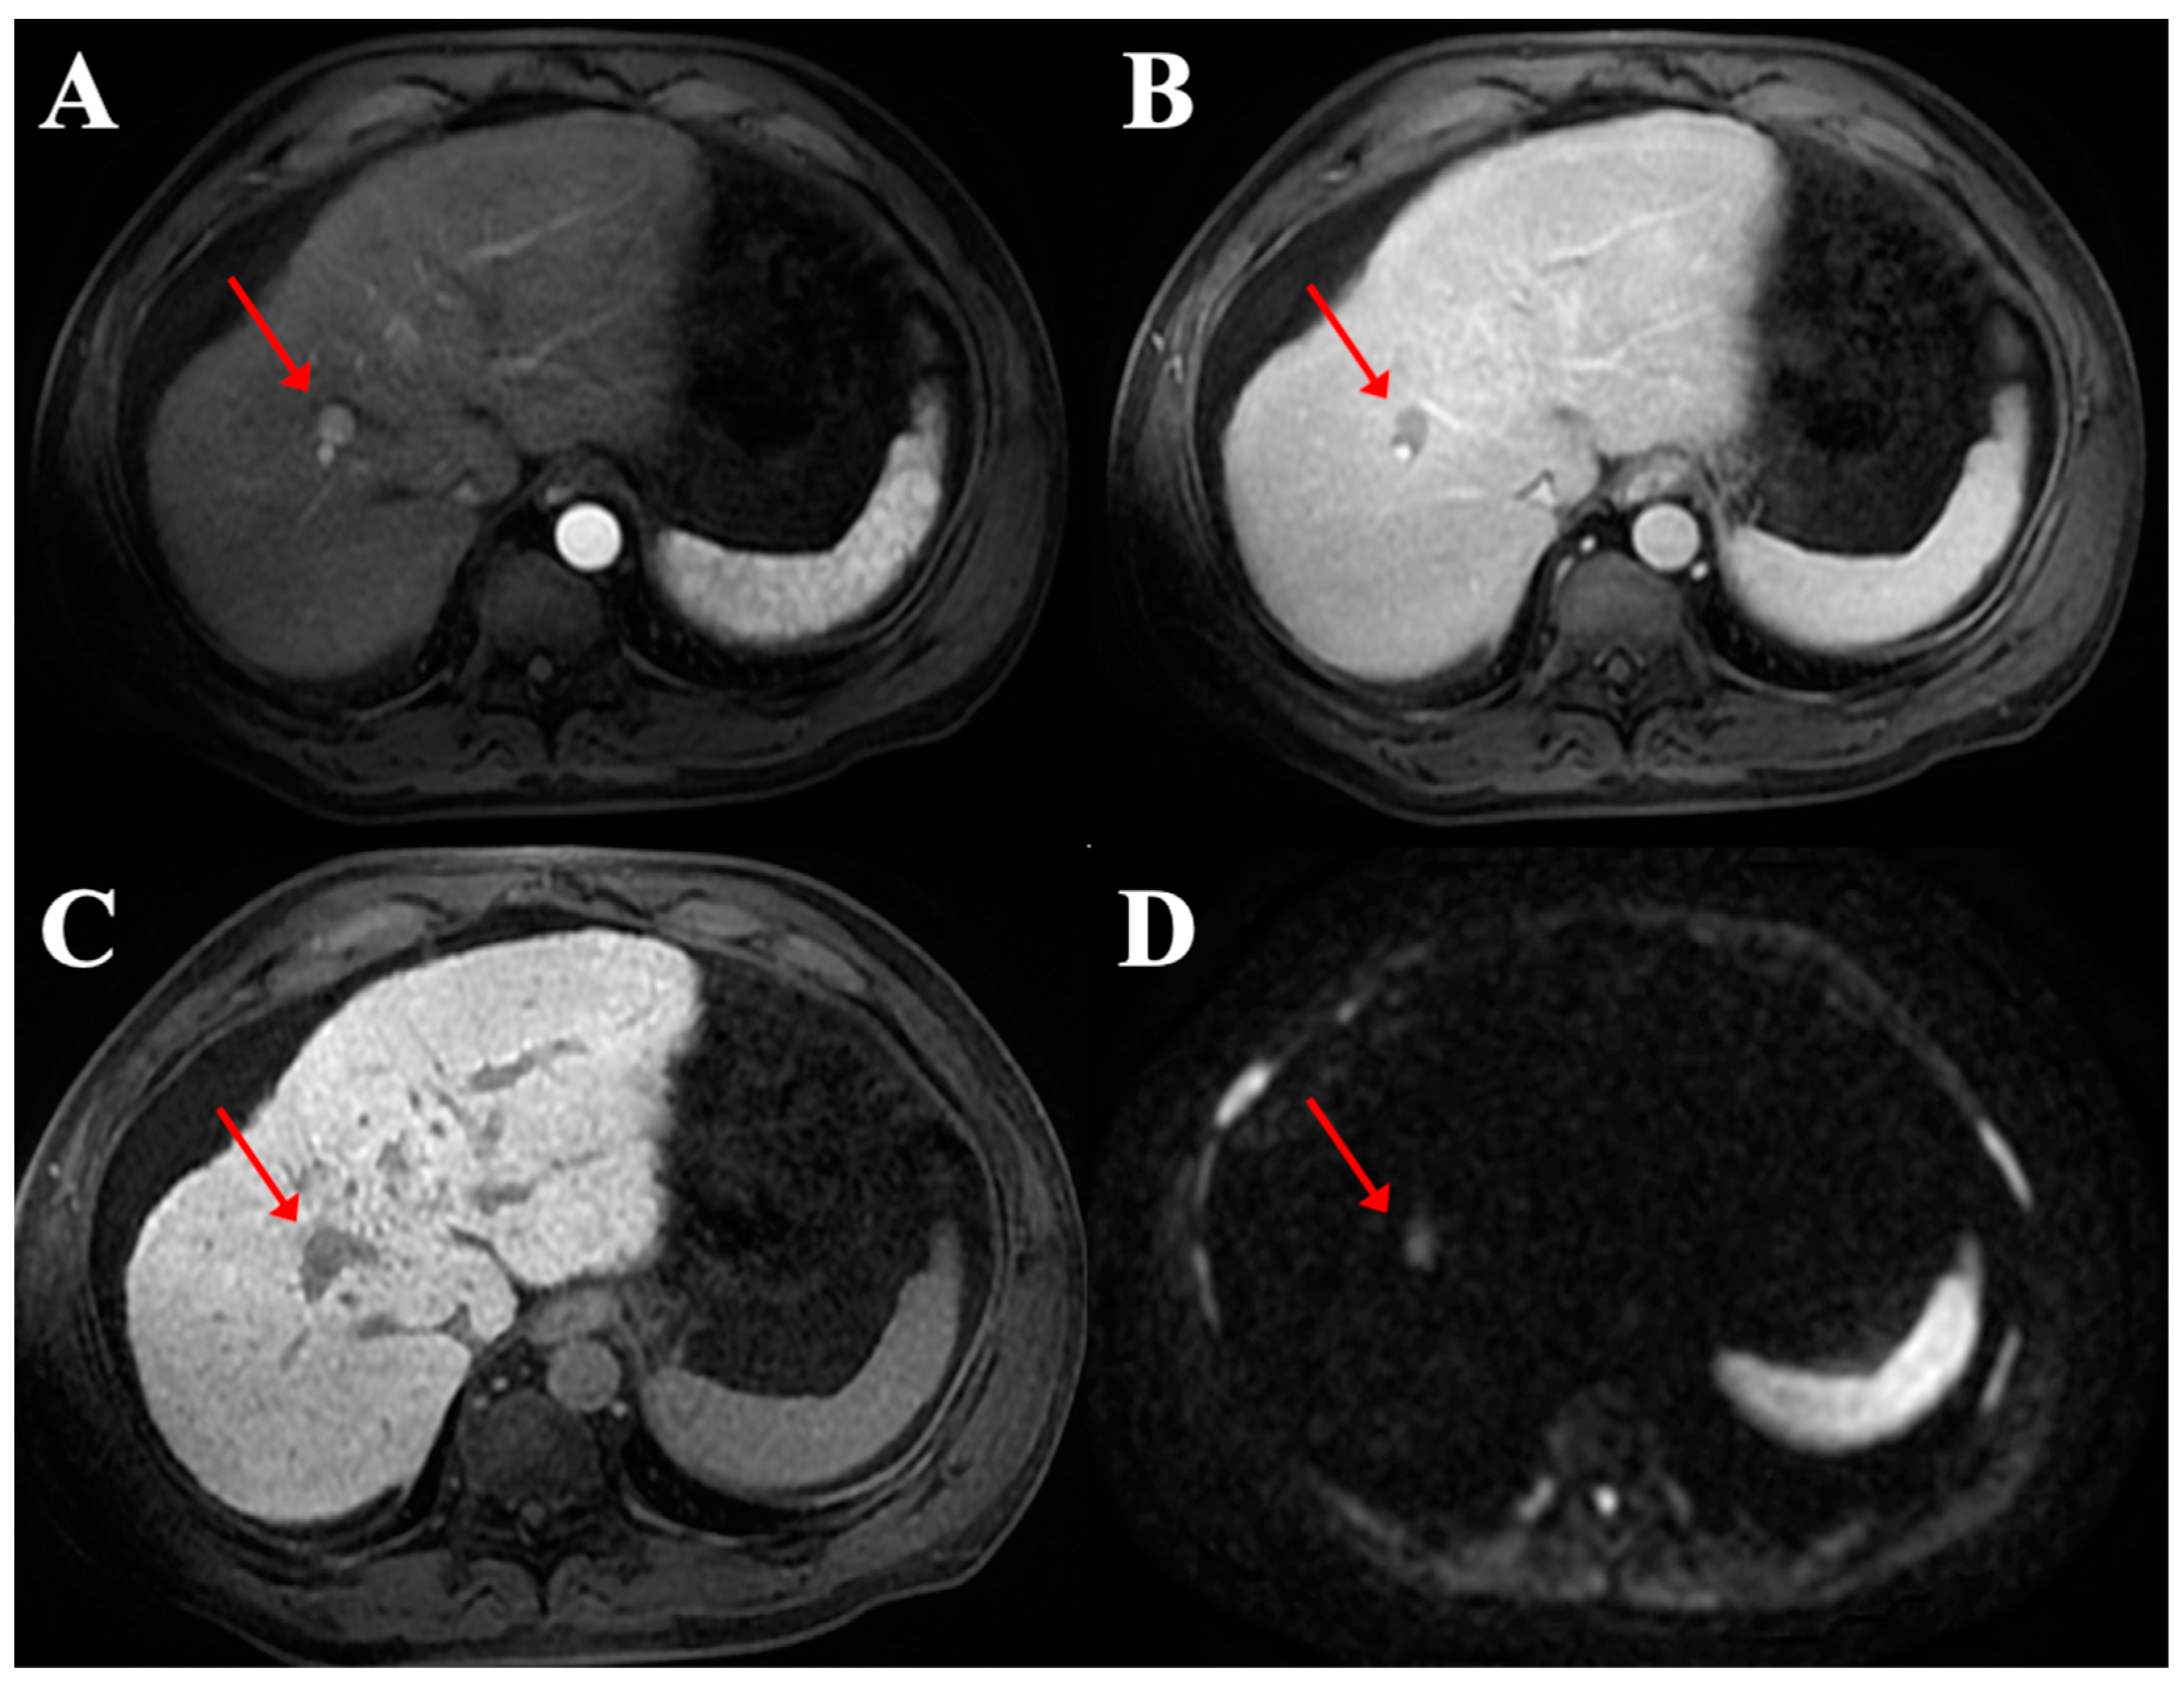

2.2. Image Analysis